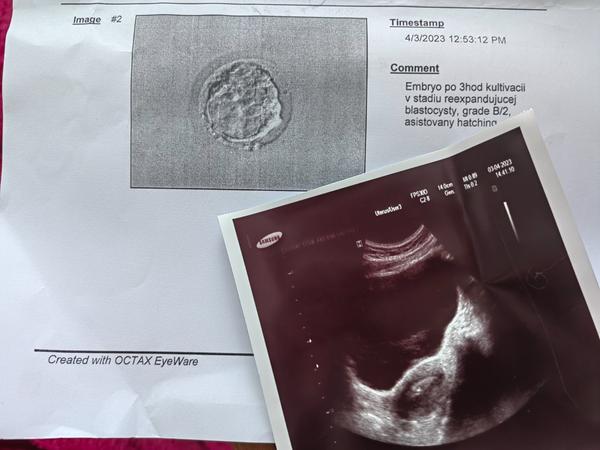

@juliasleziakova dohodnute 😄 kolko dnove ti vkladali? Mne 6 dnovu hatchujucu...

@stelush vies čo ja sa moc do toho nerozumiem, viem že bola 6dňova blastocysta a ja som si teraz dala ten asistovany hatching

@juliasleziakova tak to sme na tom cca rovnako 🙂